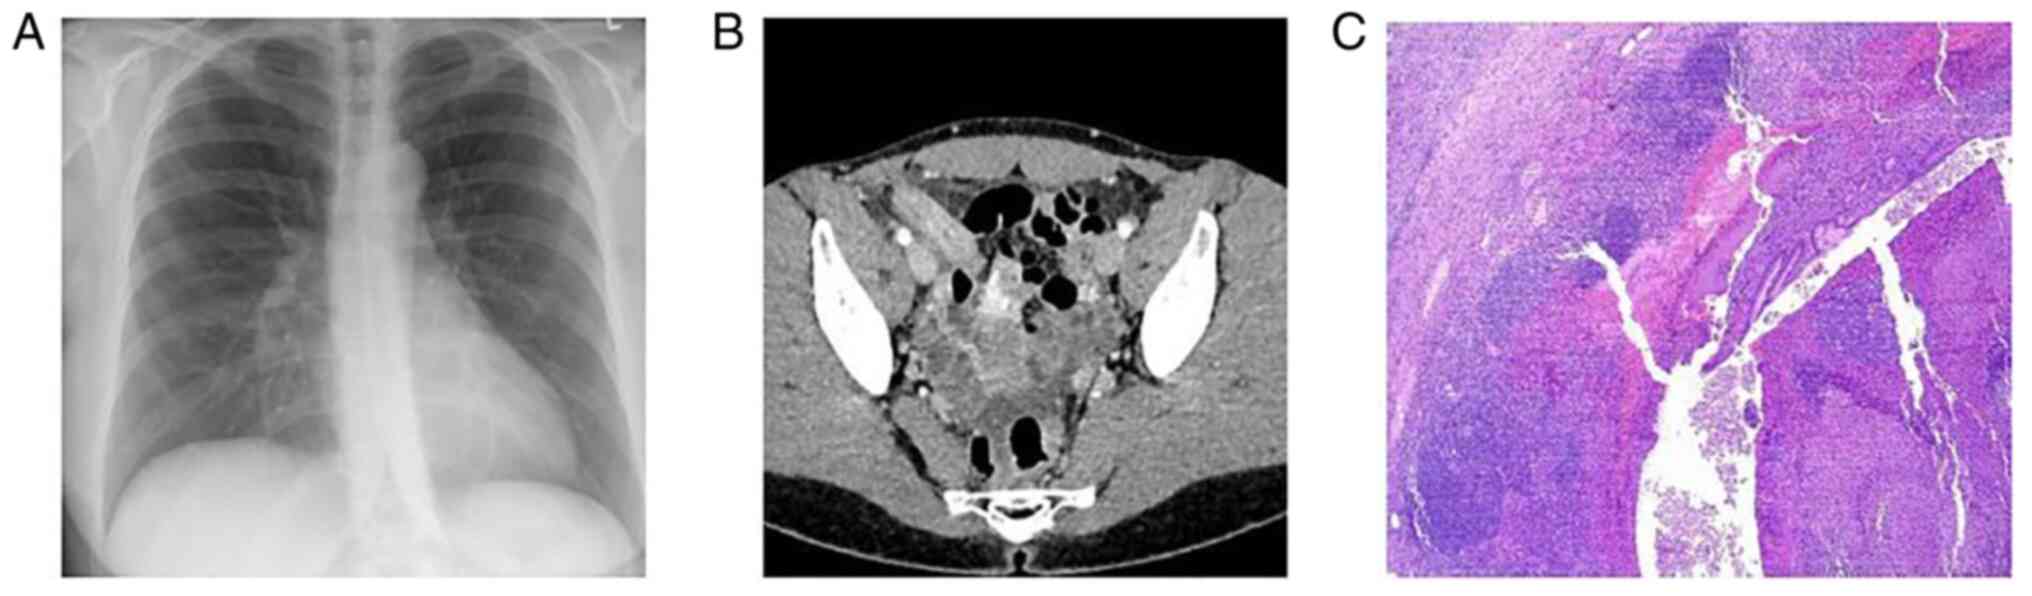

Figure 1

Case 1. (A) Normal chest X-ray. (B) Ultrasonography revealing a hyperechoic shadowing lesion consistent with an appendicolith. (C) Ultrasonography revealing a dilated appendix, measured up to 0.8 cm in the transverse dimension with surrounding fluid. (D) Hematoxylin and eosin staining; original magnification, x100. The histological analysis revealed acute appendicitis with massive inflammatory infiltrate of the appendicular wall and mesenterium.

The patient underwent abdominal and pelvic ultrasonography (U/S), which revealed a hyperechoic shadowing lesion consistent with an appendicolith (Fig. 1B) and a dilated appendix, that was measured up to 0.8 cm in the transverse dimension with surrounding fluid (Fig. 1C). The Alvarado total score was 8 out of 10 based on the symptoms and laboratory tests that supported the diagnosis of acute appendicitis. A reverse transcription-PCR (RT-PCR) test for COVID-19 was conducted as per the hospital's protocol surgery, the result of which was positive. With all COVID-19 precautions taken, an open appendectomy was conducted under general anesthesia. The histopathological examination of the appendicular tissue revealed acute appendicitis with massive inflammatory infiltrate of the appendicular wall and mesenterium (Fig. 1D).